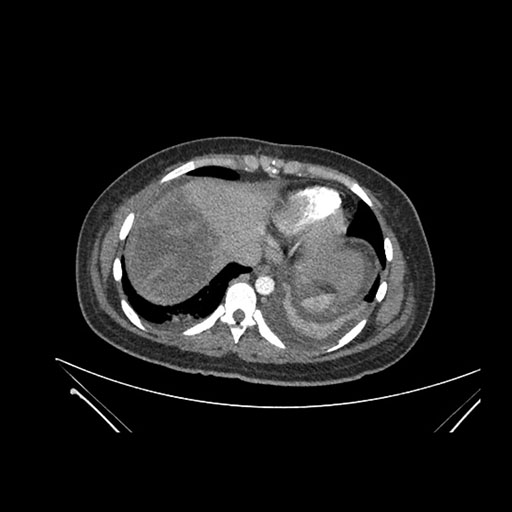

Axial Arterial

Axial Venous

Imaging analysis

Based on initial findings, which issue(s) would you be most concerned about?